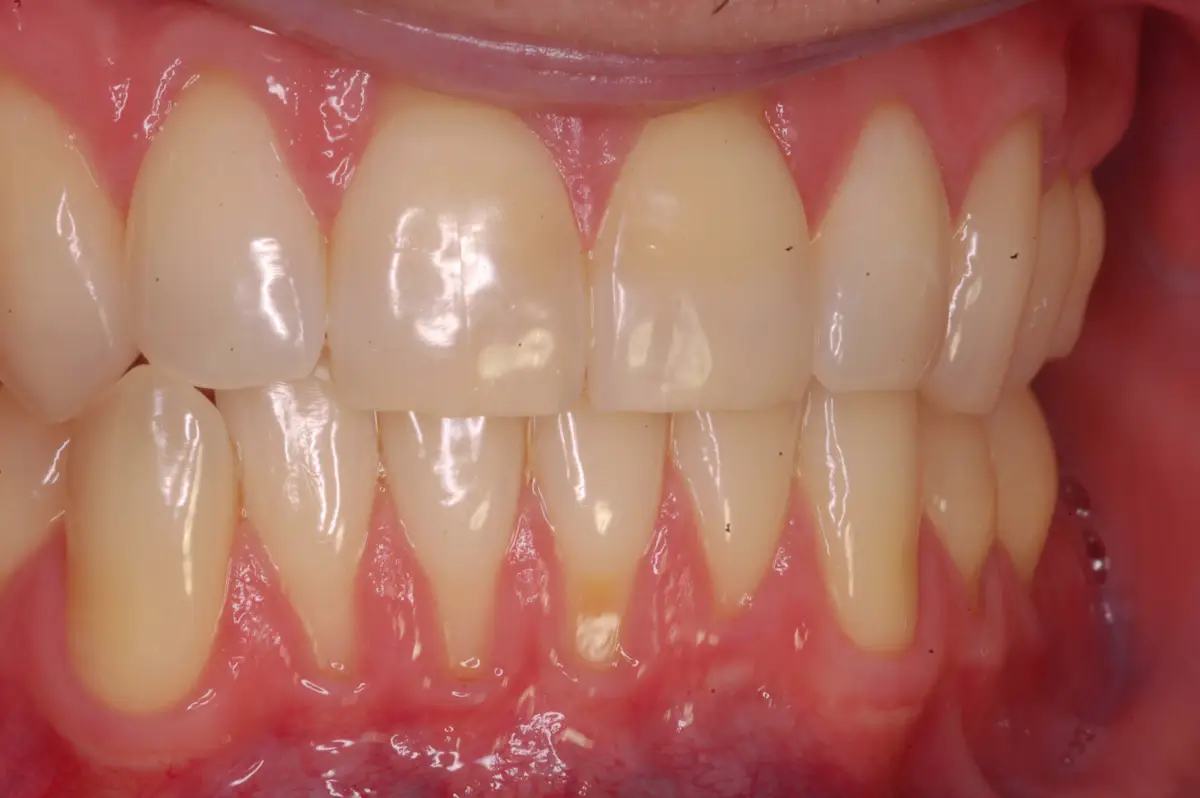

Connective Tissue Graft

before

after